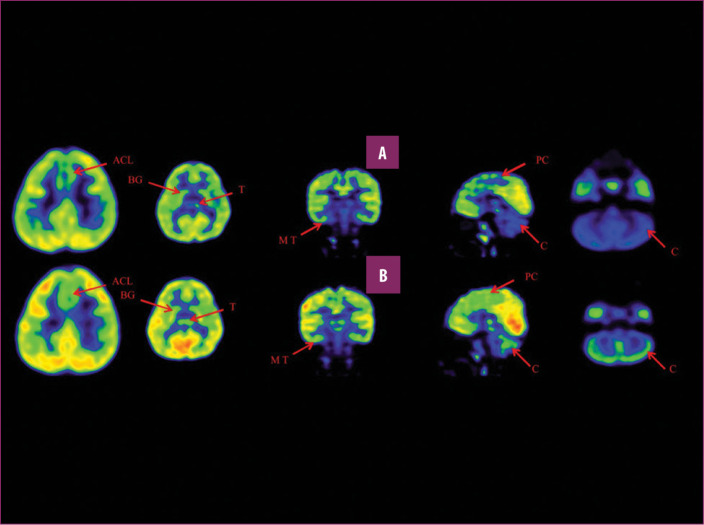

前扣帶回 (ACL)、頂葉皮層 (PC)、內側顳葉皮層 (MT)、基底神經節 (BG)、丘腦 (T) 和小腦 (C)。B 行)第一次移植后6個月后PETCT腦部掃描的干預后圖像顯示標記區域有所改善。藍色代表代謝減退區域。綠色代表正常的新陳代謝區域。圖A和B的比較顯示藍色區域顯著減少,綠色區域增加,這表明大腦的新陳代謝得到改善。

與之前的情況相比,他在矢狀面和額狀面上的體重變化有所改善;頭部、軀干和骨盆的排列也得到改善,雙側腿筋和小腿肌肉的緊繃感也有所減輕。患者開始執行雙手任務。在認知方面,由于他定期上學,他的注意力持續時間和久坐耐力也得到了改善。GMFM評分從60.67提高到67.75;GMFCS等級由Level3提升至Level2;和FIM評分從97分提高到99分。在比較第一次細胞治療之前和之后七個月期間進行的腦部PETCT掃描結果時,前扣帶葉、頂葉皮層、內側顳葉皮層、丘腦、基底神經節和小腦(表格1)。